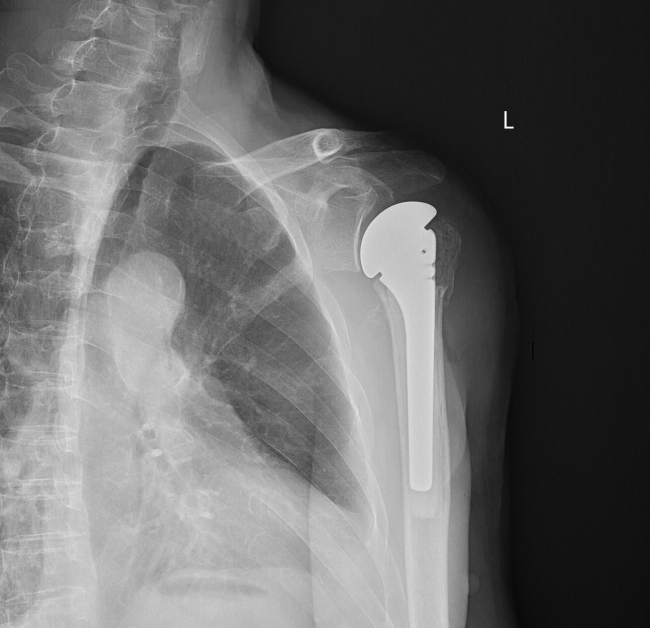

骨一科团队为患者进行专业评估后,制定最佳手术方案,决定为朱先生实施人工肱骨头置换手术。骨一科主任唐新文介绍说,人工肩关节置换术是使用金属材料和高分子塑料置入人体替换受损骨和软骨来缓解疼痛等症状的手术方法,而人工肱骨头置换手术解决了部分复杂肱骨近端骨折患者的手术难题,具有创伤小、恢复快、效果好等优势,因术后可获得较为满意的肩关节活动功能,而受到广大患者的青睐,但此项技术却对手术医师的操作准确性及熟练程度有着严格要求。

通过术前精心设计,在麻醉科的配合下,医务人员成功为朱先生实施了人工肱骨头置换手术,手术过程顺利,术中出血少。术后第一天,患者患肩已能在无痛状态下主动完成握拳、伸指、腕关节环绕、肘关节屈伸运动。在科室医护团队的协助指导下,朱先生康复顺利,不日即将出院。